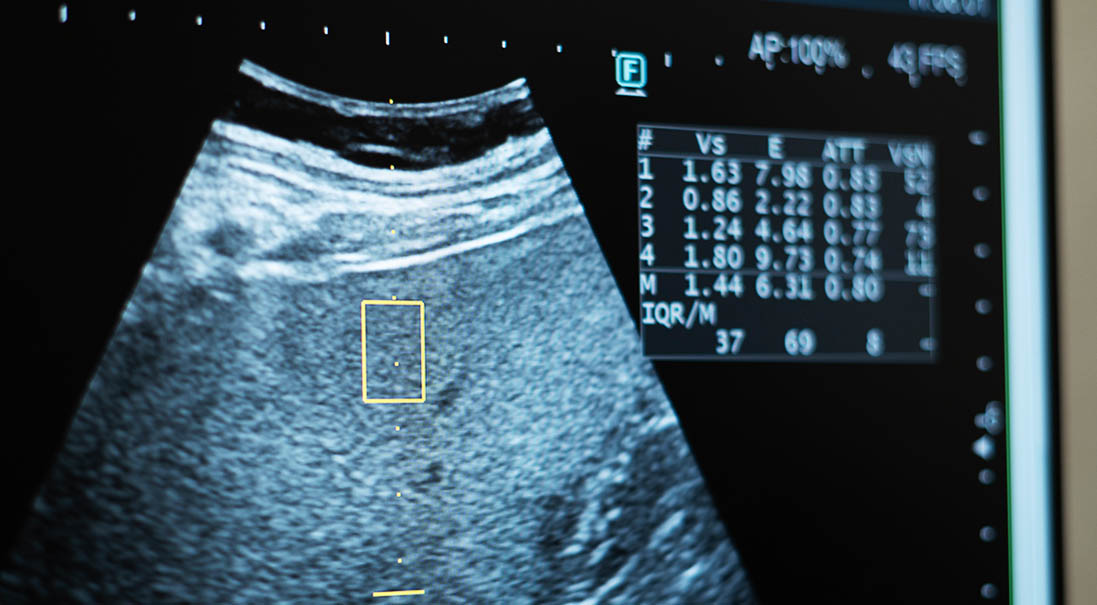

• 腹部エコー検査

腹部内臓系のスクリーニング(肝、胆嚢、膵臓、腎臓など)、胆石や腎結石の有無、腹痛の原因検査が可能です。

検査時間は約15分で痛みなどは一切ないため、安心して受けていただけます。